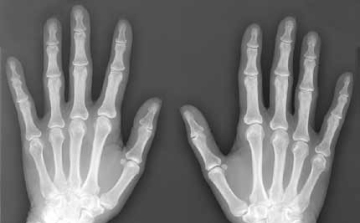

A magzatvíz visszafordíthatja a csontok öregedését

A magzatvízben lévő őssejtek újjáéleszthetik az öregedő és gyenge csontokat - állítják brit kutatók, akik szerint felfedezésük segíthet genetikai betegséggel született gyerekeken, idős embereken és űrhajósokon is.